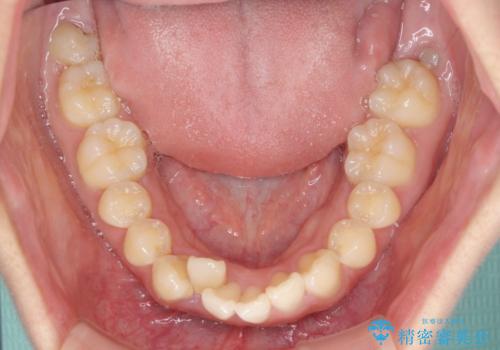

上下前歯の叢生をインビザラインできれいに

- 前歯のデコボコを気にして来院された患者様です。

前歯が重なっていることで口元が閉じにくくなっていたため、歯列全体の側方への拡大と、歯と歯の間を少し削ってスペースを獲得することとしました。

下顎前歯は後戻りを起こしやすいため、舌側を細いワイヤーで固定し、マウスピース型リテーナーで保定を行うこととしました。